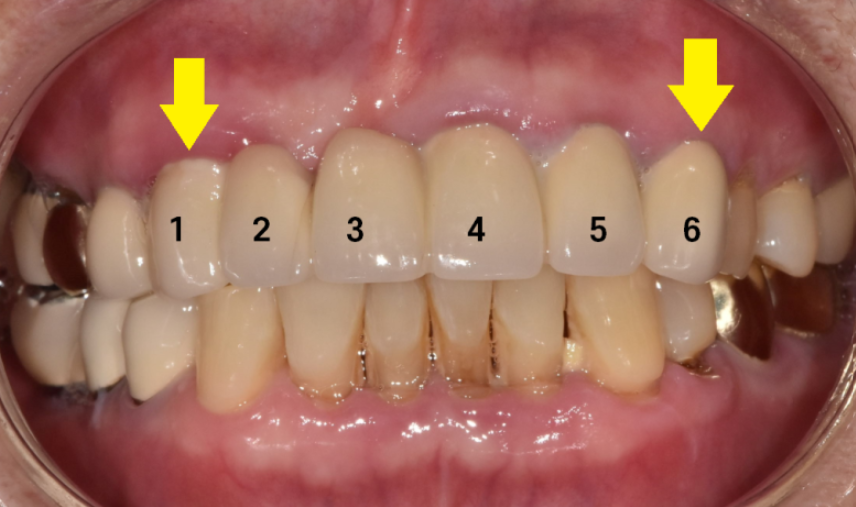

아래 앞니는 자연치아이고

위에 치아 6개를 보철하신 상태네요~

송곳니부터 송곳니까지요.